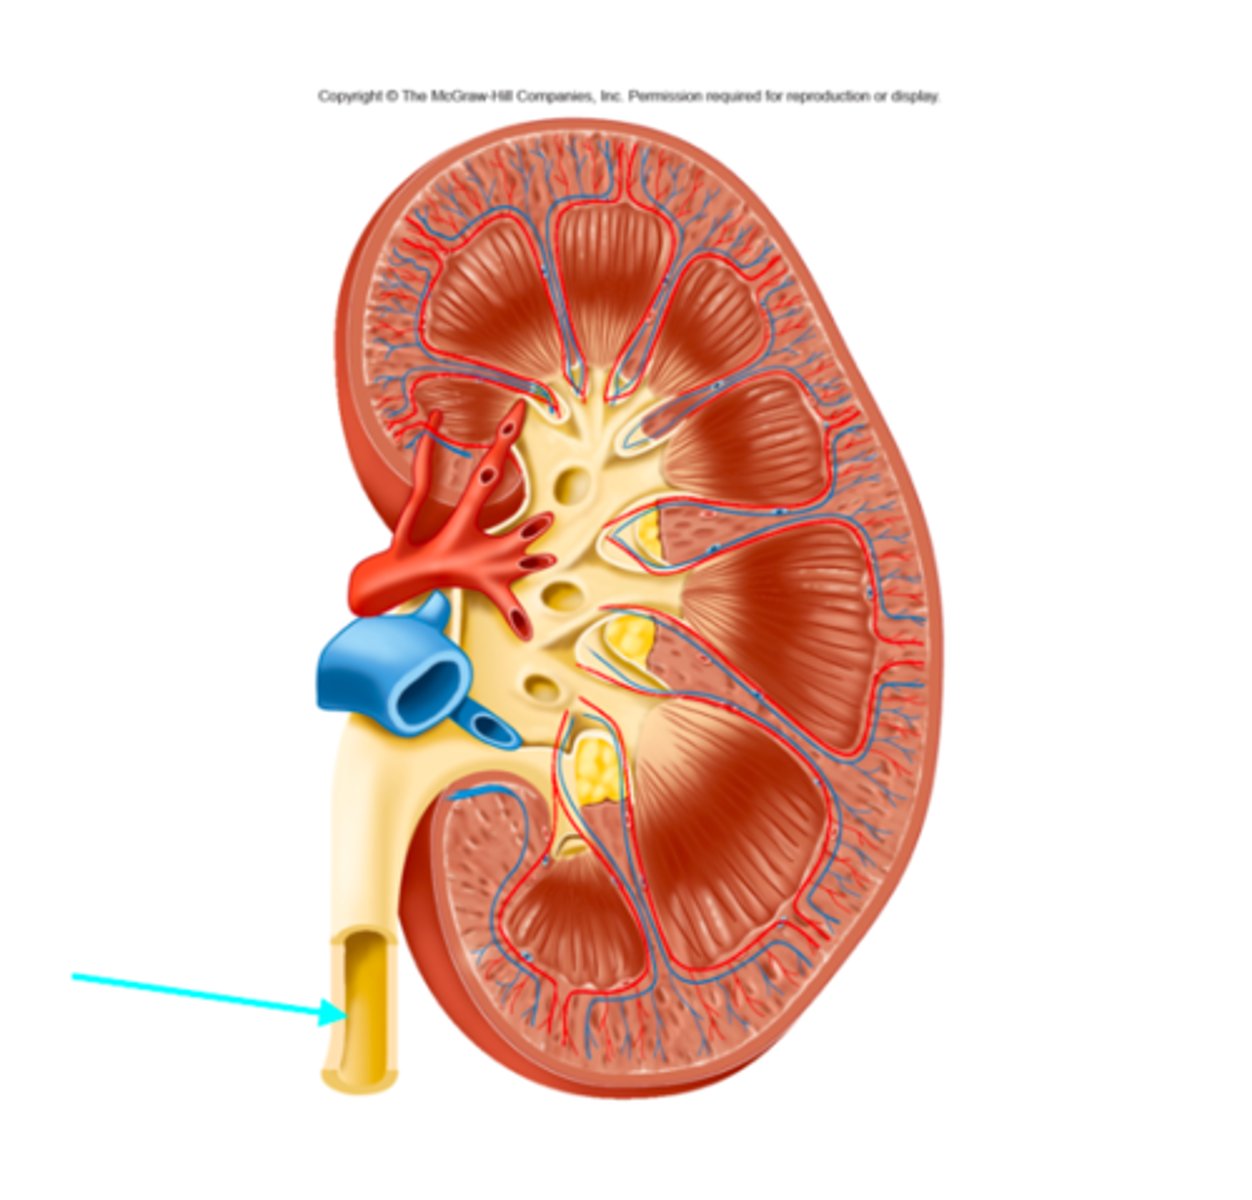

What structure of the kidneys is the blue arrow pointing at?

Ureter

What structure of the kidneys is the blue arrow pointing at?